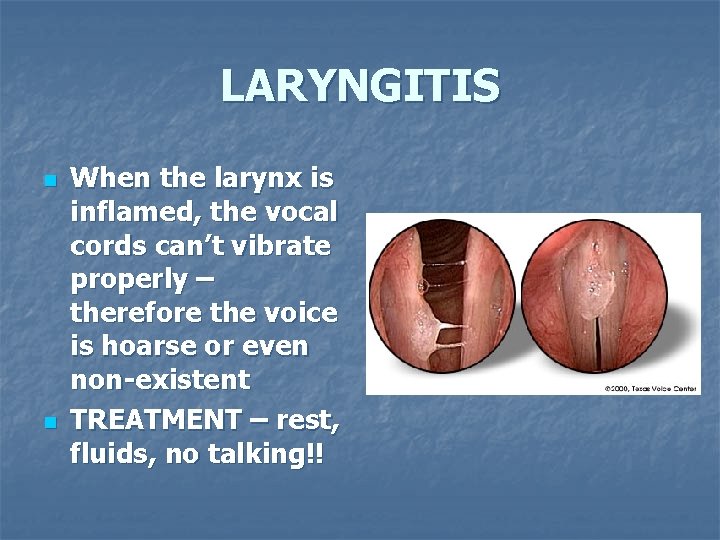

LARYNGITIS n n Laryngitis is an inflammation of the larynx (vocal cords) CAUSES: virus allergies straining of voice

LARYNGITIS n n When the larynx is inflamed, the vocal cords can’t vibrate properly – therefore the voice is hoarse or even non-existent TREATMENT – rest, fluids, no talking!!